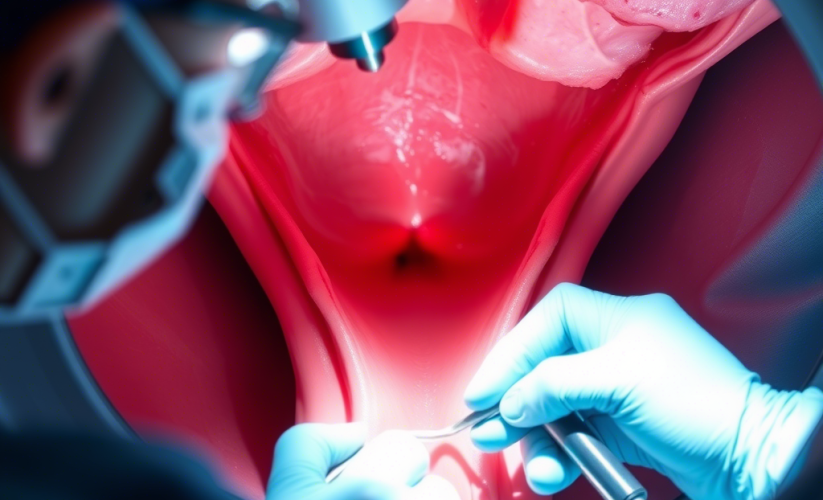

خوشفرم کردن واژن با تزریق ژل به واژن یا تزریق ژل به بیکینی:

فرم دهی به واژن زمانی فکر برخی بانوان را درگیر میکند که با افزایش سن یا زایمان یا کاهش وزن واژن حالت خود را از دست می دهد و از فرم طبیعی خود خارج می شود لذا برای درمان این مشکل جهت فرمدهی به واژن خود اقدام مینمایند.

برای فرم دهی به واژن چندین پروسیجر بسیار تاثیرگذار انجام می شود که در کوتاهترین زمان نتایج قابل توجی در بر دارد.

- فرم دهی به واژن با تزریق ژل و چربی به واژن در تهران توسط دکتر ماندانا اکبری

- فرم دهی به واژن با تزریق ژل و چربی بسته به کیس های مختلف متفاوت است.